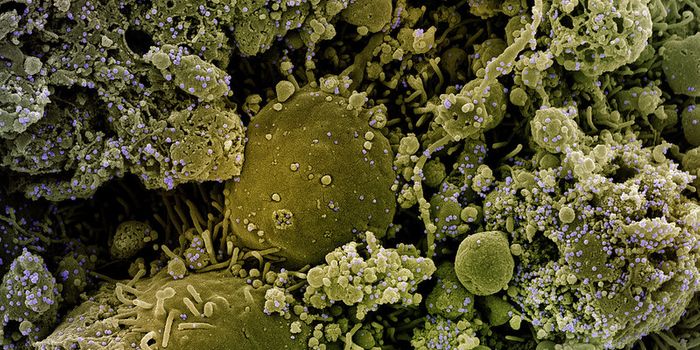

SEP 05, 2024Cell & Molecular BiologyCorynebacterium matruchotii ia a common bacterium that lives in human dental plaque; a colony is seen in this image by S ...